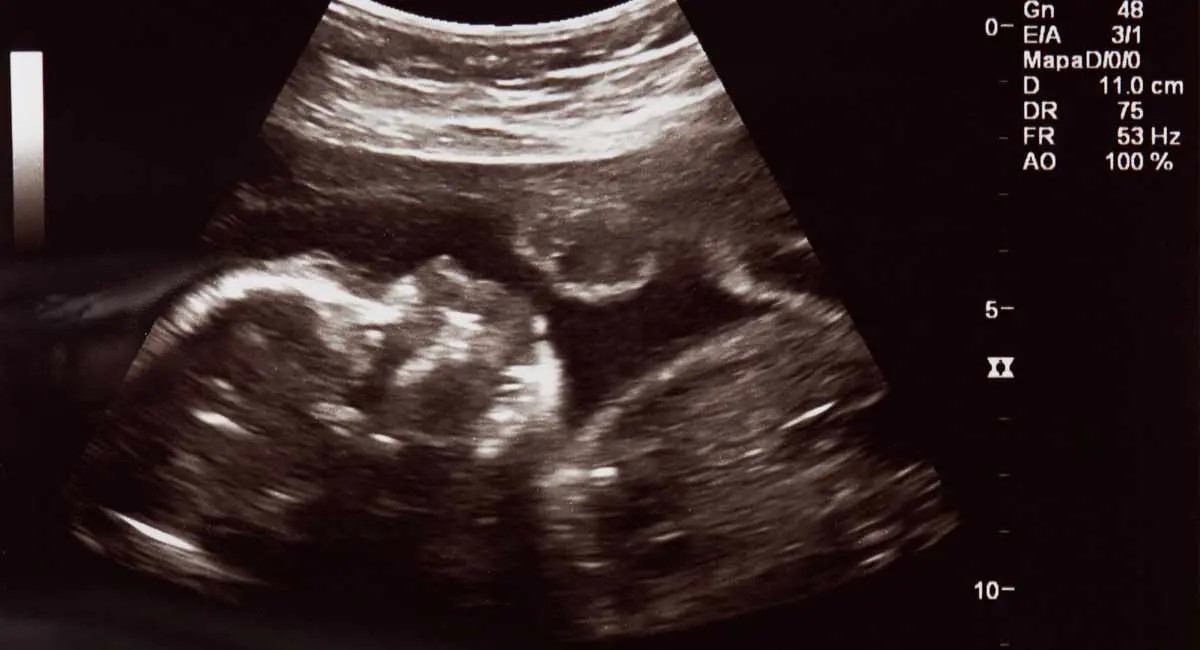

Is it the fact that the unborn did not suffer as much? Then again, science has proven that the unborn try to evade the abortion doctor as he comes for them.

1753543815566.webp

Sarah Cleveland is a board certification Registered Diagnostic Medical Sonographer. Fifteen years ago, she assisted in an amniocentesis that was done under ultrasound guidance. In an amniocentesis, a needle is inserted into a woman’s uterus to withdraw amniotic fluid, which is then tested to detect fetal abnormalities. It is not an abortion procedure, and the target of the needle is not the baby. Sarah describes what she witnessed happening in the mother’s uterus when the procedure began:

… I placed the transducer over the uterus and saw a baby approximately 18 weeks gestation on the screen. He was kicking, playful, and happy. Then the doc inserted the needle.

Immediately, the baby knew something was in his space. That something was different. As I held the transducer to guide the needle to a safe area away from the placenta and away from Baby, I saw Baby dart away from where we were in the uterus and move as far away as possible to the other side of the womb. He stopped kicking and playing… Then the heart rate. His little heart rate sky rocketed. He was scared. In fact, I am convinced he was terrified.

After only about 20 seconds of withdrawing fluid, the needle was out. … I watched Baby for a few minutes longer, while the parents conversed with one another. The Baby slowly, eventually, came out of the corner and the heart rate slowly decelerated.

READ: Abortionists describe impact of learning D&E abortions

Cleveland points out that “the baby was not the target” and “the needle never once touched him.” So imagine what might happen in an abortion: